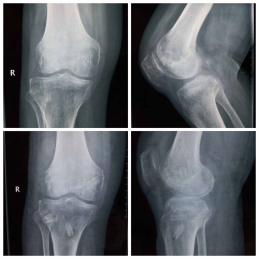

近日,我院运动创伤与关节镜外科成功治疗一例陈旧性膝关节脱位复合后交叉韧带断裂及后外侧复合体断裂患者,自体移植肌腱重建后交叉韧带及后外侧复合体。病人目前已顺利出院。

患者,男性,65岁,因车祸伤致右膝膝关节不稳及活动受限7月余收住我院运动创伤与关节镜外科。患者7月前因车祸伤导致全身多发伤:颅脑损伤、胸腰椎多节段损伤、多处肋骨骨折、左下肢胫骨骨折外院多次手术治疗。后因右膝关节严重不稳就诊于我科徐洪港副主任医师,患者就诊时右膝关节严重失稳定,静息状态下右膝关节可诱发多向不稳定及脱位,患者极度痛苦,受伤后患者长期卧床无法自行行走。因患者高龄并且损伤严重,曾多次就诊我省及外省多家三甲医院,因患者伤情较重,均未收住。患者入院后科室多次组织专家讨论,考虑患者目前陈旧性损伤伤情严重、右膝关节多组韧带损伤,并且因长期废用导致右下肢骨质条件极差又极大的增加了患者的治疗难度。我科徐洪港副主任医师术前结合患者病史、体检及必要的影像学检查,制定了详细的手术方案及预案,术中采用自体移植肌腱关节镜下解剖重建后交叉韧带同期微创有限切口自体肌腱移植重建后外侧复合体(LaPrade技术)。手术顺利,术中术后患者无输血,术后第二天即可扶拐杖下地活动,迅速恢复生活能力。